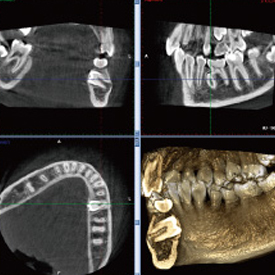

精度が高い診査・診断&安心・安全な治療歯科用CT- Computer Tomograghy -

CTとはComputer Tomograghyの略で、日本語ではコンピューター断層撮影と訳されます。 これは、X線とコンピューターによって、歯や骨の位置や形態などを3D画像で立体的に撮影するための医療機器です。

血管や神経の位置を立体的に把握し、骨量、骨密度を正確に確認できるため、インプラント治療の際にはCTによる診査・診断が必須となっています。

多くの歯科医院では、CTを撮影するために外部のスキャニングセンターへ撮影に出向く必要がありますが、当クリニックでは院内にCTを設置しているため、レントゲンと同じように院内で撮影し、即座に診ることができます。